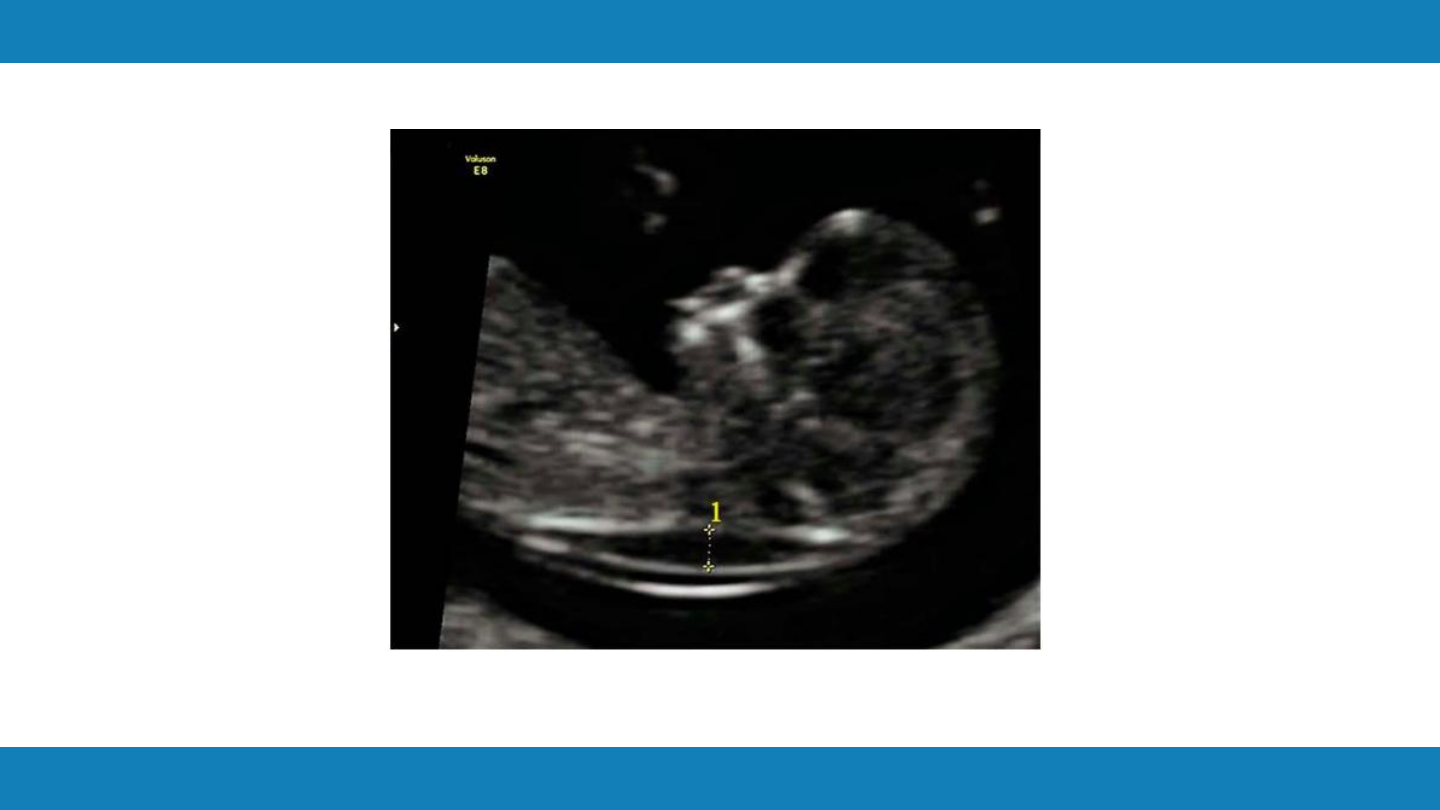

超声遗传学标志物筛查

胎儿颈项透明层(

NT

其他软指标

颈项透明层

background image